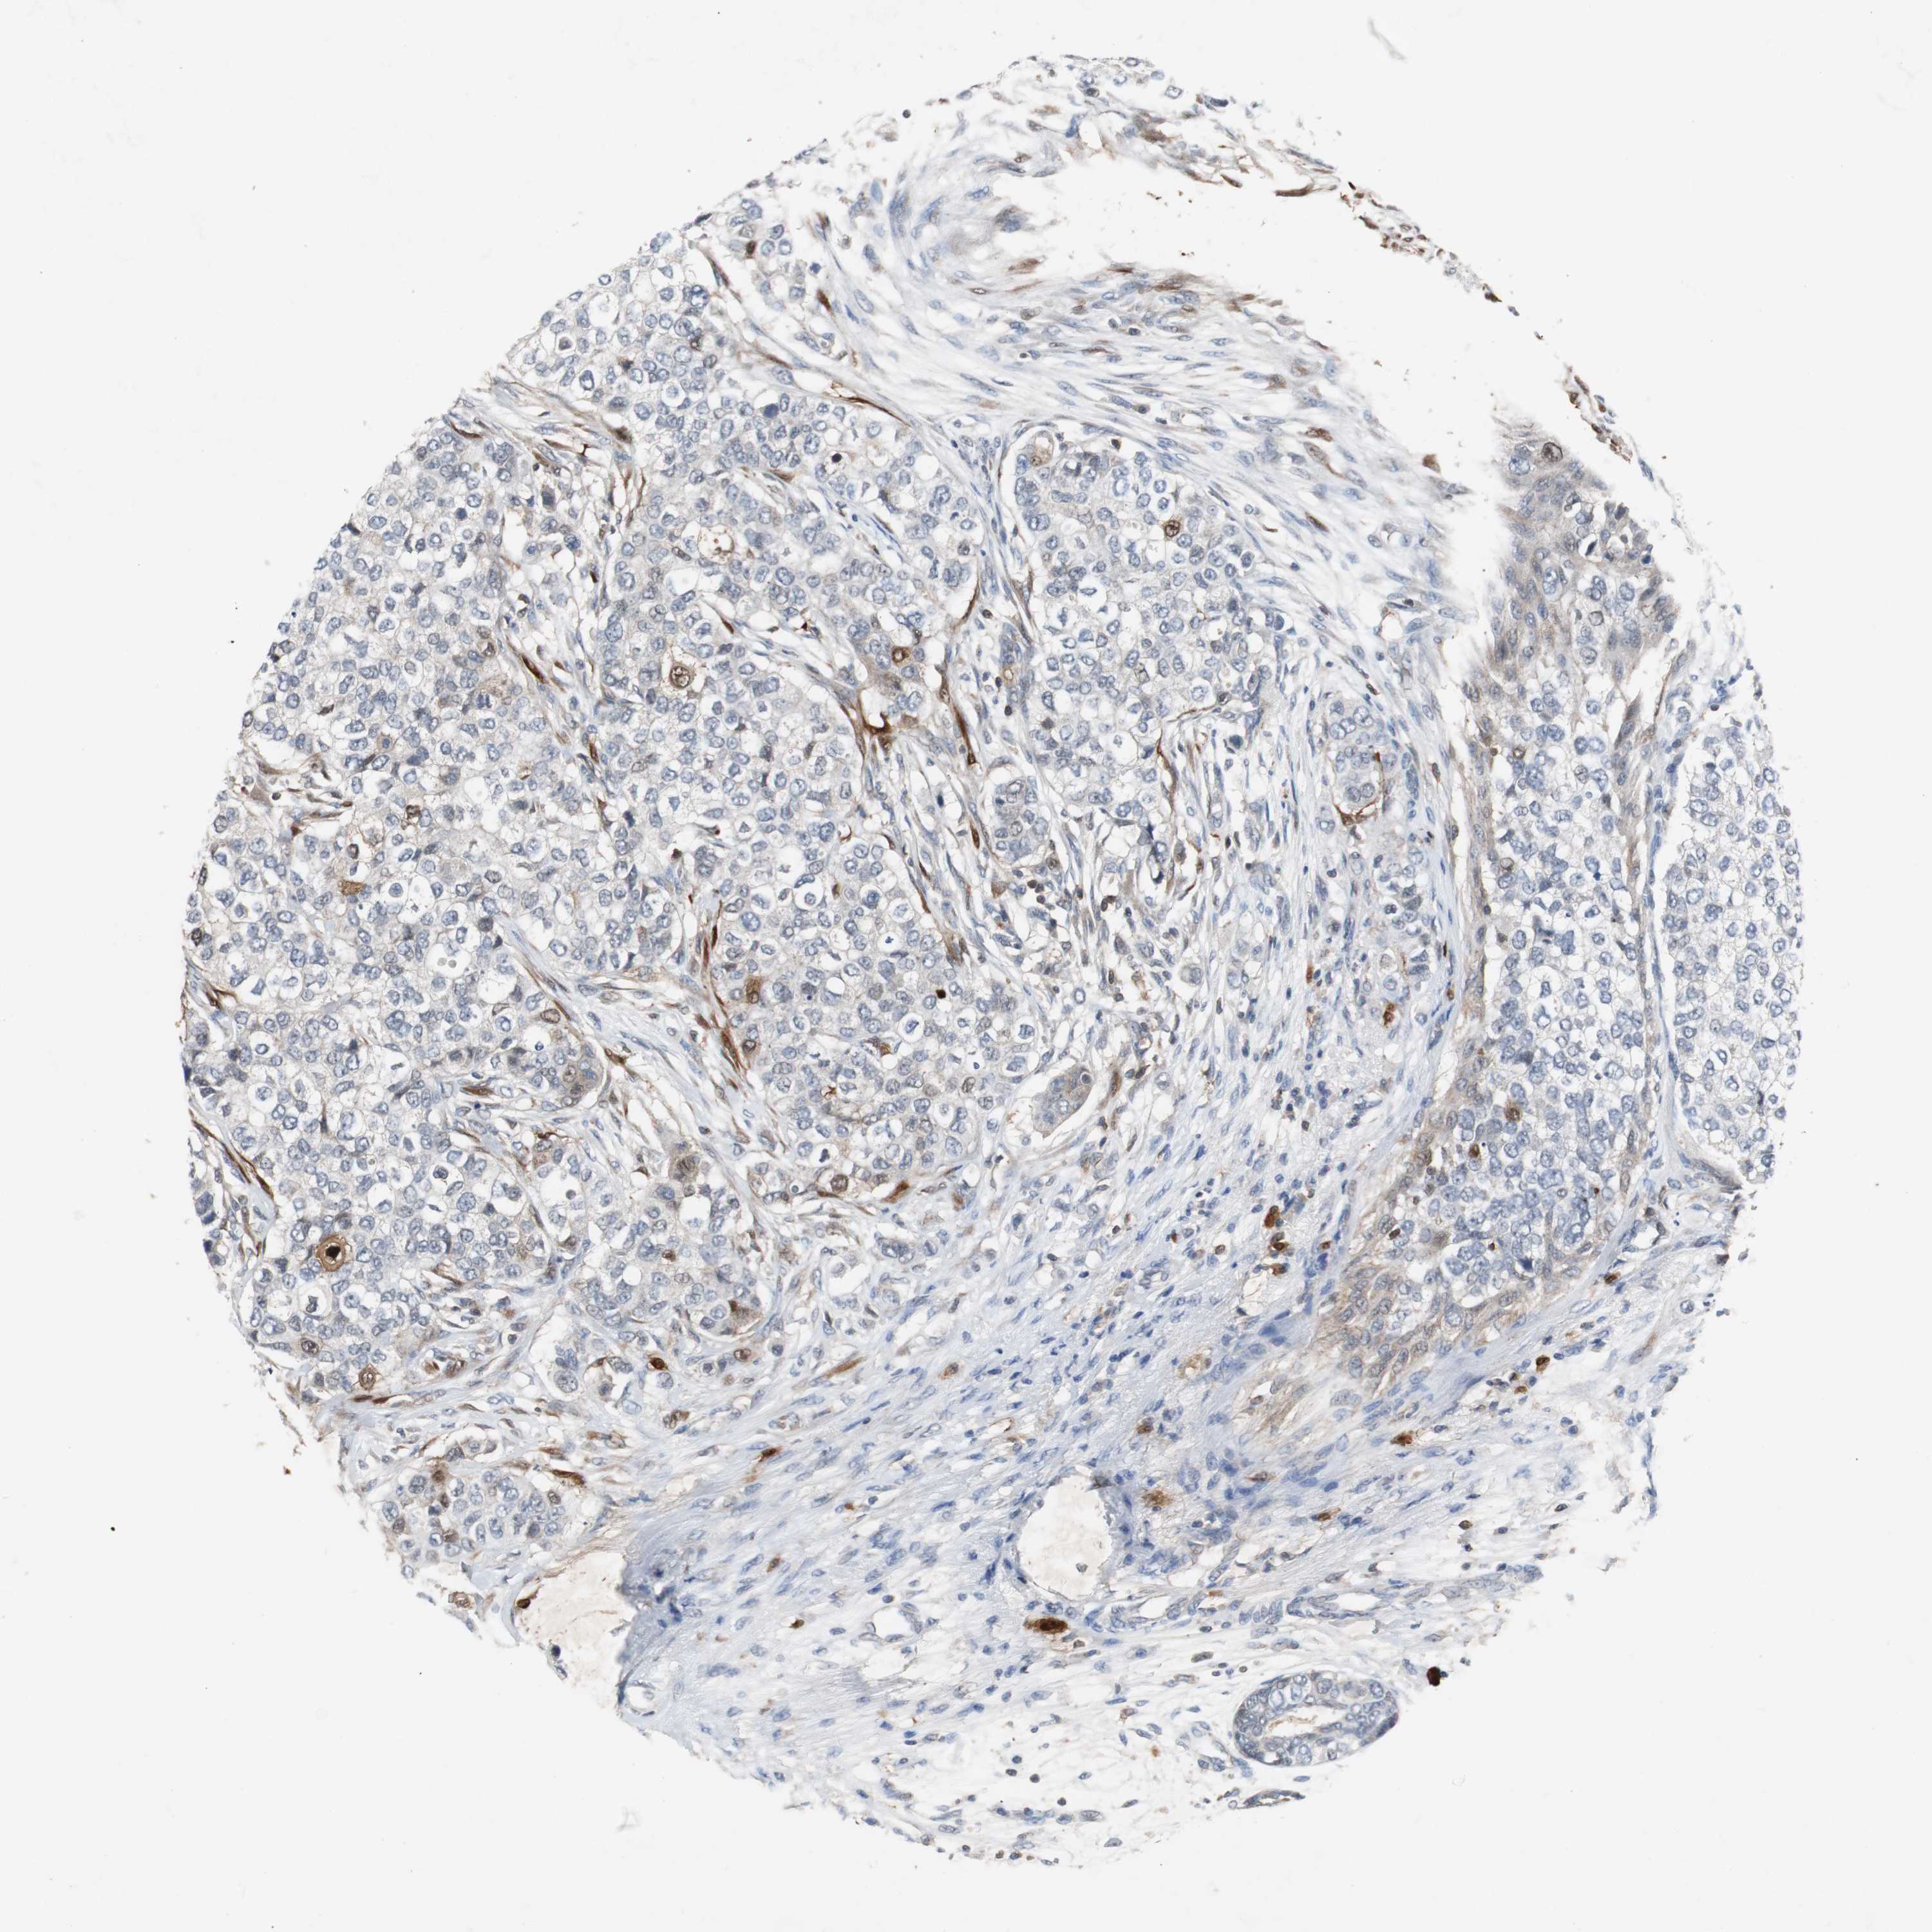

CANCER BREAST CANCER Show tissue menu

BRCA TCGA BRCA VALIDATION PROTEIN EXPRESSION